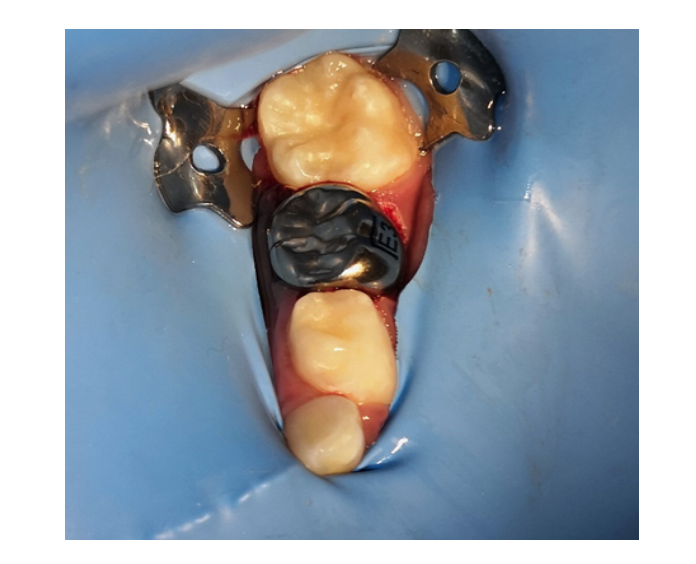

Selladores

/Resinas